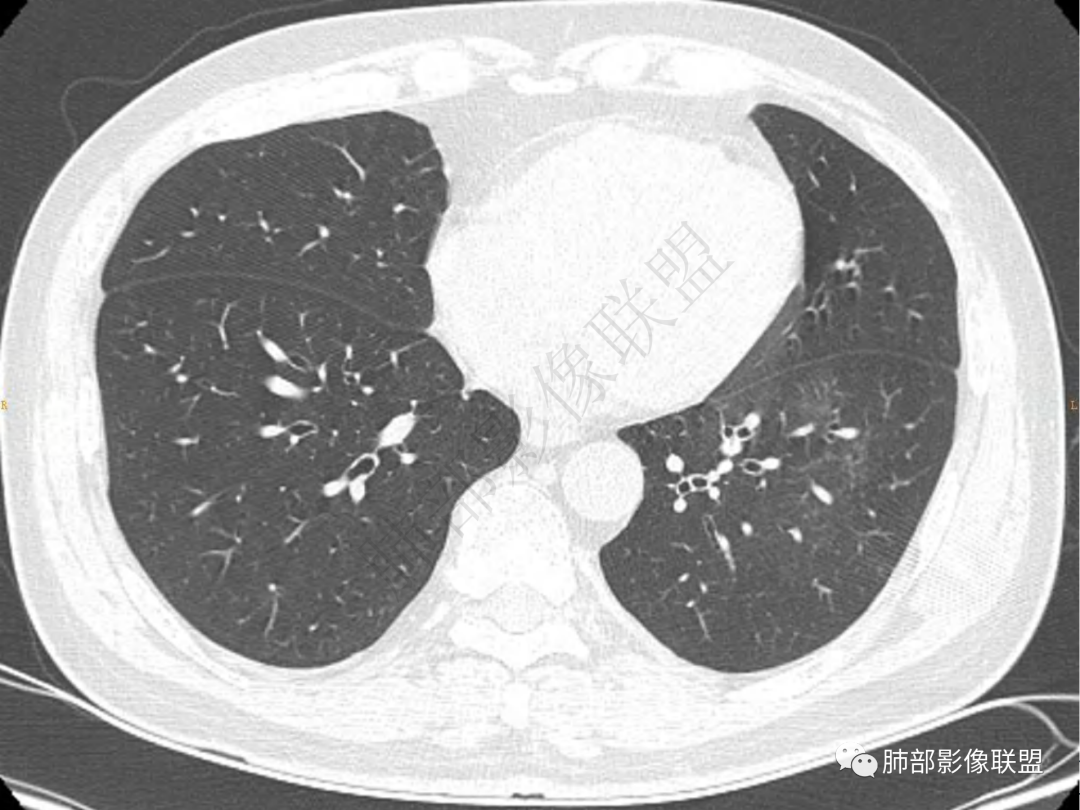

2.左肺下叶团片影,跨背段及内前基底段,实性部分类椭圆形,密度不甚均匀,可见毛刺及棘状突起,未见典型分叶及胸膜凹陷。病灶上下缘可见相应肺段支气管旁进侧出,管壁轻度增厚,未见狭窄阻塞。

3.周边较大范围磨玻璃影,边界相当模糊,小叶增厚明显。注意叶裂另一侧、左肺舌段亦可见磨玻璃影及增厚的小叶间隔。未见明确卫星病灶。

4.实性部分不均匀环形强化并显示一小范围低密度坏死区或空洞。较之肺窗,整体纵隔窗范围较小,提示病灶并不十分密实。抑或为不同时段图像。

肺脓肿:可宽基底与胸膜相连,附近胸膜增厚——炎性特点

肺脓肿:边界模糊不清,或者块影为类圆形,无明显分叶,边缘平直为主,刀切征——炎性特点三、病灶周围特点:肺脓肿:病灶非远端有片状GGO——炎性特点四、近端支气管阻塞:肺脓肿:常有引流支气管伴管壁增厚或者支气管沿洞壁走行。五:坏死壁:肺脓肿:大多壁厚,少数壁薄,没有壁结节,内壁清楚光整——炎性特点